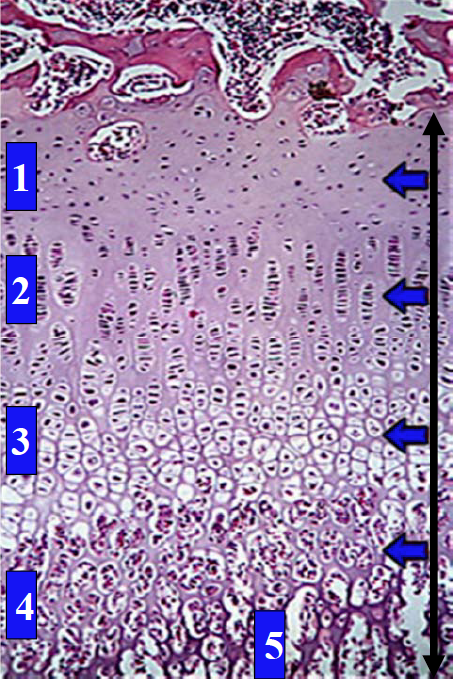

Growth Plate: Identify the zones

Identify the zone of proliferation in this growth plate of hyaline cartilage.